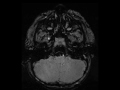

Vasospasm Secondary to Subarachnoid Hemorrhage

This case demonstrates vasospasm in the setting of acute subarachnoid hemorrhage. On the axial FLAIR sequence, there is abnormal hyperintensity in the suprasellar, ambient, and interpeduncular cisterns compatible with hemorrhage in the basal cisterns. The axial T2 and susceptibility weighted images demonstrate abnormal hypointense signal within the prepontine space and extending towards the right cerebellopontine angle cistern. The postcontrast sagittal T1-weighted image demonstrates hemorrhage in the prepontine and premedullary spaces. The 3-D MIP reconstructions from the 3D time of flight MRA of the head demonstrates smooth concentric marked narrowing of the distal vertebral arteries, vertebral confluence, and proximal basilar artery. Along with rebleeding, cerebral vasospasm is a major source of morbidity and mortality in the setting of acute subarachnoid hemorrhage. Symptoms typically are present from 4-10 days following the hemorrhage.